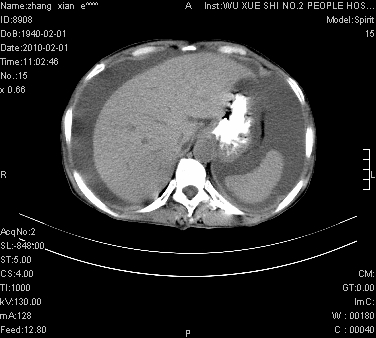

标题: CT24434:70岁 女 腹胀,腹水原因待查 [打印本页]

标题: CT24434:70岁 女 腹胀,腹水原因待查

大量腹水,脾脏囊性占位,子宫颈占位,右侧腹股沟淋巴结肿大,建议+c,先查妇科。

大量腹水,脾囊肿可能性大,建议增强

腹盆腔大量积液,子宫增大,子宫颈增大外形不规则,内见低密度影,膀胱后壁显示不清,右腹股沟肿大淋巴结,脾脏囊性占位,子宫颈占位,子宫颈癌?建议增强。

大量腹水,右肾、脾囊肿可能性大          考虑左侧附件区占位,建议增强